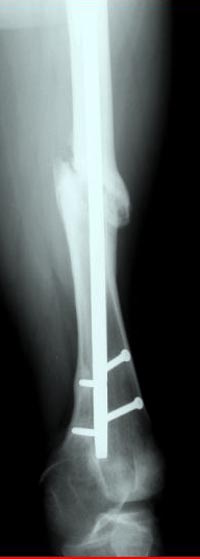

Лечение бедра - ургентное оперативное лечение антеградным с минимально рассверливанием, фиксацией с минимальным диаметром штифта и плюс irrigation and debridment и с закрытием поперечной до 10 см раны на уровне перелома в день поступления.

Снимки представлены: 1 мес; 3 мес; 1 год; 2 года, предоперационные и ротационная КТ грамма